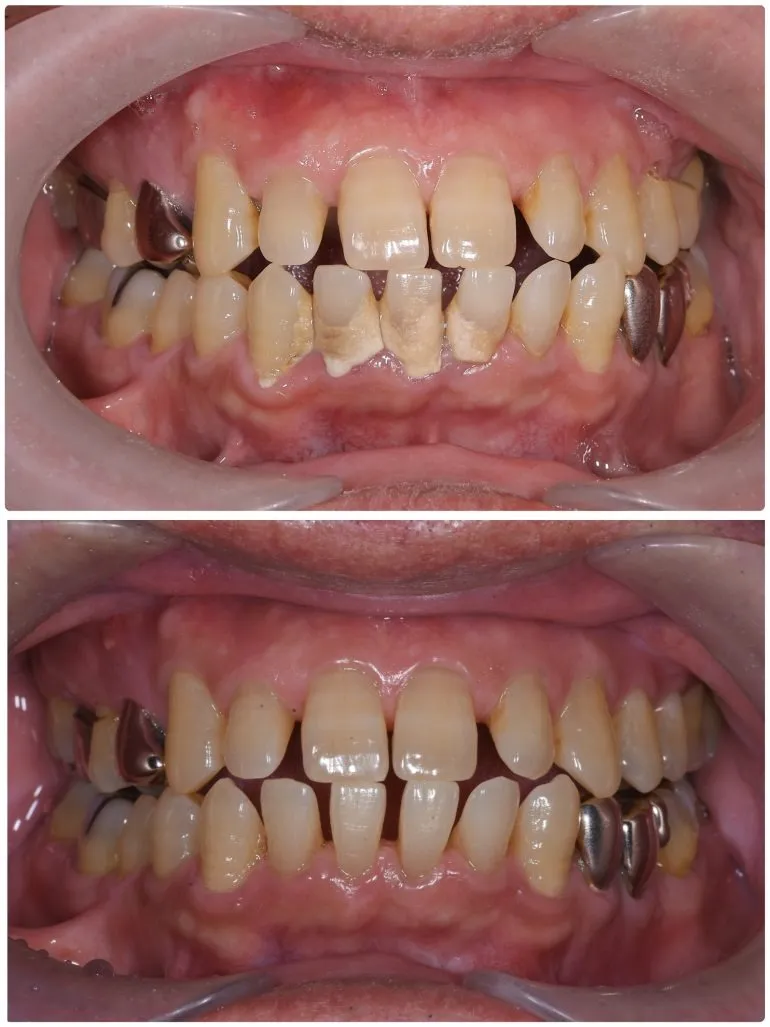

エアフローを使用したクリーニング

治療名

クリーニング

治療説明

治療回数

1回

副作用・リスク

呼吸器系の疾患や、薬剤によるアレルギー、妊娠・授乳期など、お身体の状態によってはエアフローが使用できない場合があります。

料金

保険適用

歯石がこびりついている場合も、保険適用でここまで綺麗になります。

最近歯医者さんに行けていない、または歯医者さんが怖いという方も、ぜひ一度ご相談ください。